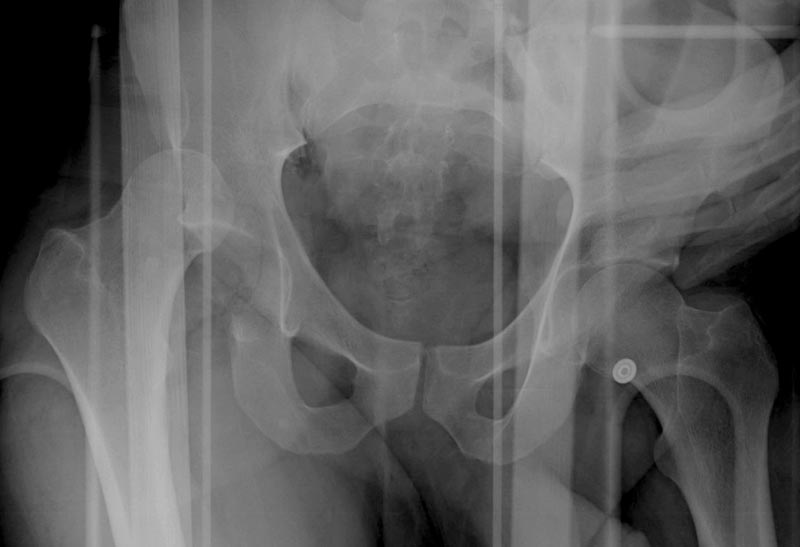

Выставлена на обсуждение (только одна проекция) рентгенограмма больного 25 лет, поступившего в приемное отделение, молодой дежурный врач сомневается в тактике лечения и спрашивает совета.

С его слов, больной стабилен,травму получил в результате автоаварии.Подскажите, что делать?Джолдас Кульджанов

Джолдас,

Кроме вывиха виден перелом задней стенки, насчет задней колонны не уверен (видна линия перелома дистальнее ацет. крыши - подвздошная проекция или СТ помогли бы прояснить ситуацию). Поэтому с такой ситуации только закрытое вправление без рефиксации фрагмента задней стенки может привести к рецидиву вывиха (с чем имел неприятность столкнуться не так давно).

Alexander Chelnokov 17 Ноябрь 2004, 17:21

Вопрос, не иначе, с каким-то подвохом...

На первый взгляд, бедро надо вправить, наложить вытяжение, и дообследовать - Judet views, CT вертлужной впадины, чтобы оценить дефект задней стенки. Вероятно, придется делать остеосинтез заднего края.

5:24 Рентгенограмма таза, вызывают врача ортопеда (снимок N1), его диагноз: закрытый переломо-вывих правого тазабедренного сустава, получает добро на закрытую репозицию в приемном отделении